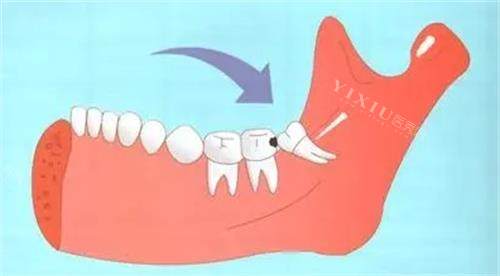

刚进诊所,前台小姐姐就注意到我捂着腮帮子的痛苦表情,赶紧递来冰袋让我冷敷,还优先给我安排了就诊。诊室里的氛围意外温馨,墙上贴着卡通版的牙齿科普漫画,牙椅旁边甚至放着个小玩偶,让我原本紧张到嗓子眼的心稍稍放下。接诊的赵医生拿着口镜检查时特别温柔,发现我的智齿是横着长的阻生齿,卡在牙槽骨里,难怪疼,他调出我的口腔 CT 影像,用手机上的 3D 模型给我演示拔牙过程,哪里需要切开牙龈、哪里要小心避开神经,讲得明明白白,还说会尽量减少创伤,术后修复更快。